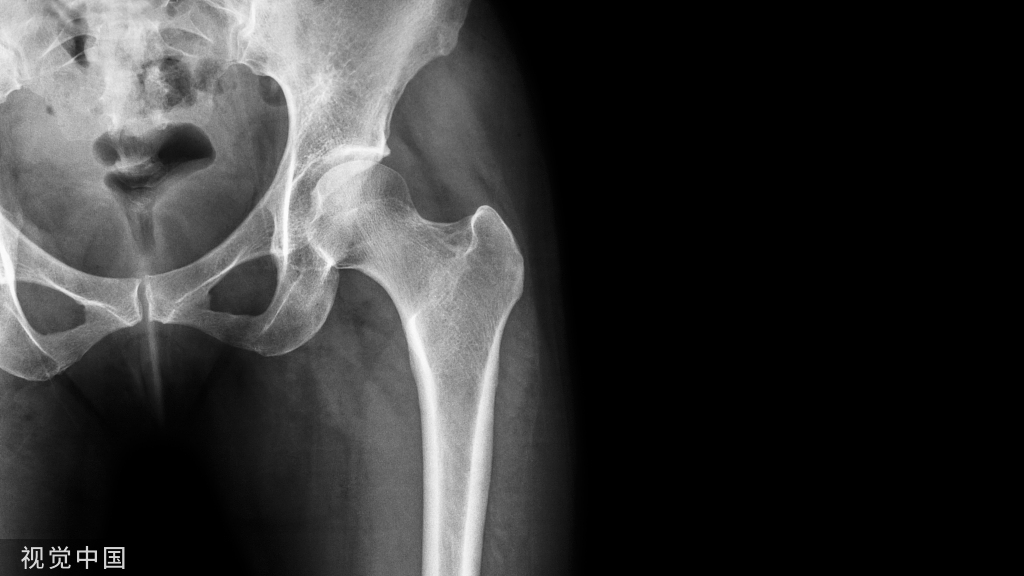

(五)胸腰椎